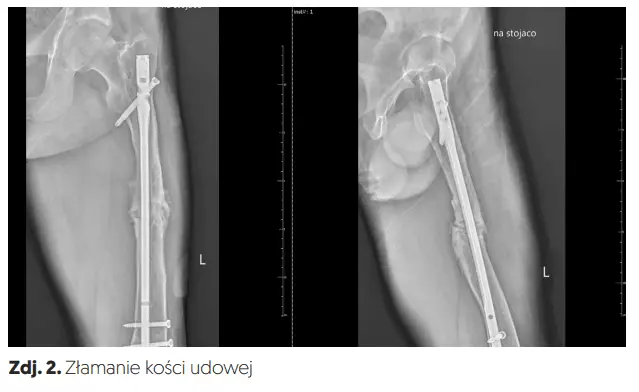

Złamanie trzonu kości udowej najczęściej wymaga leczenia chirurgicznego polegającego na zespoleniu określonych elementów kostnych np. płytką lub gwoździem śródszpikowym (zdj. 1, 2).